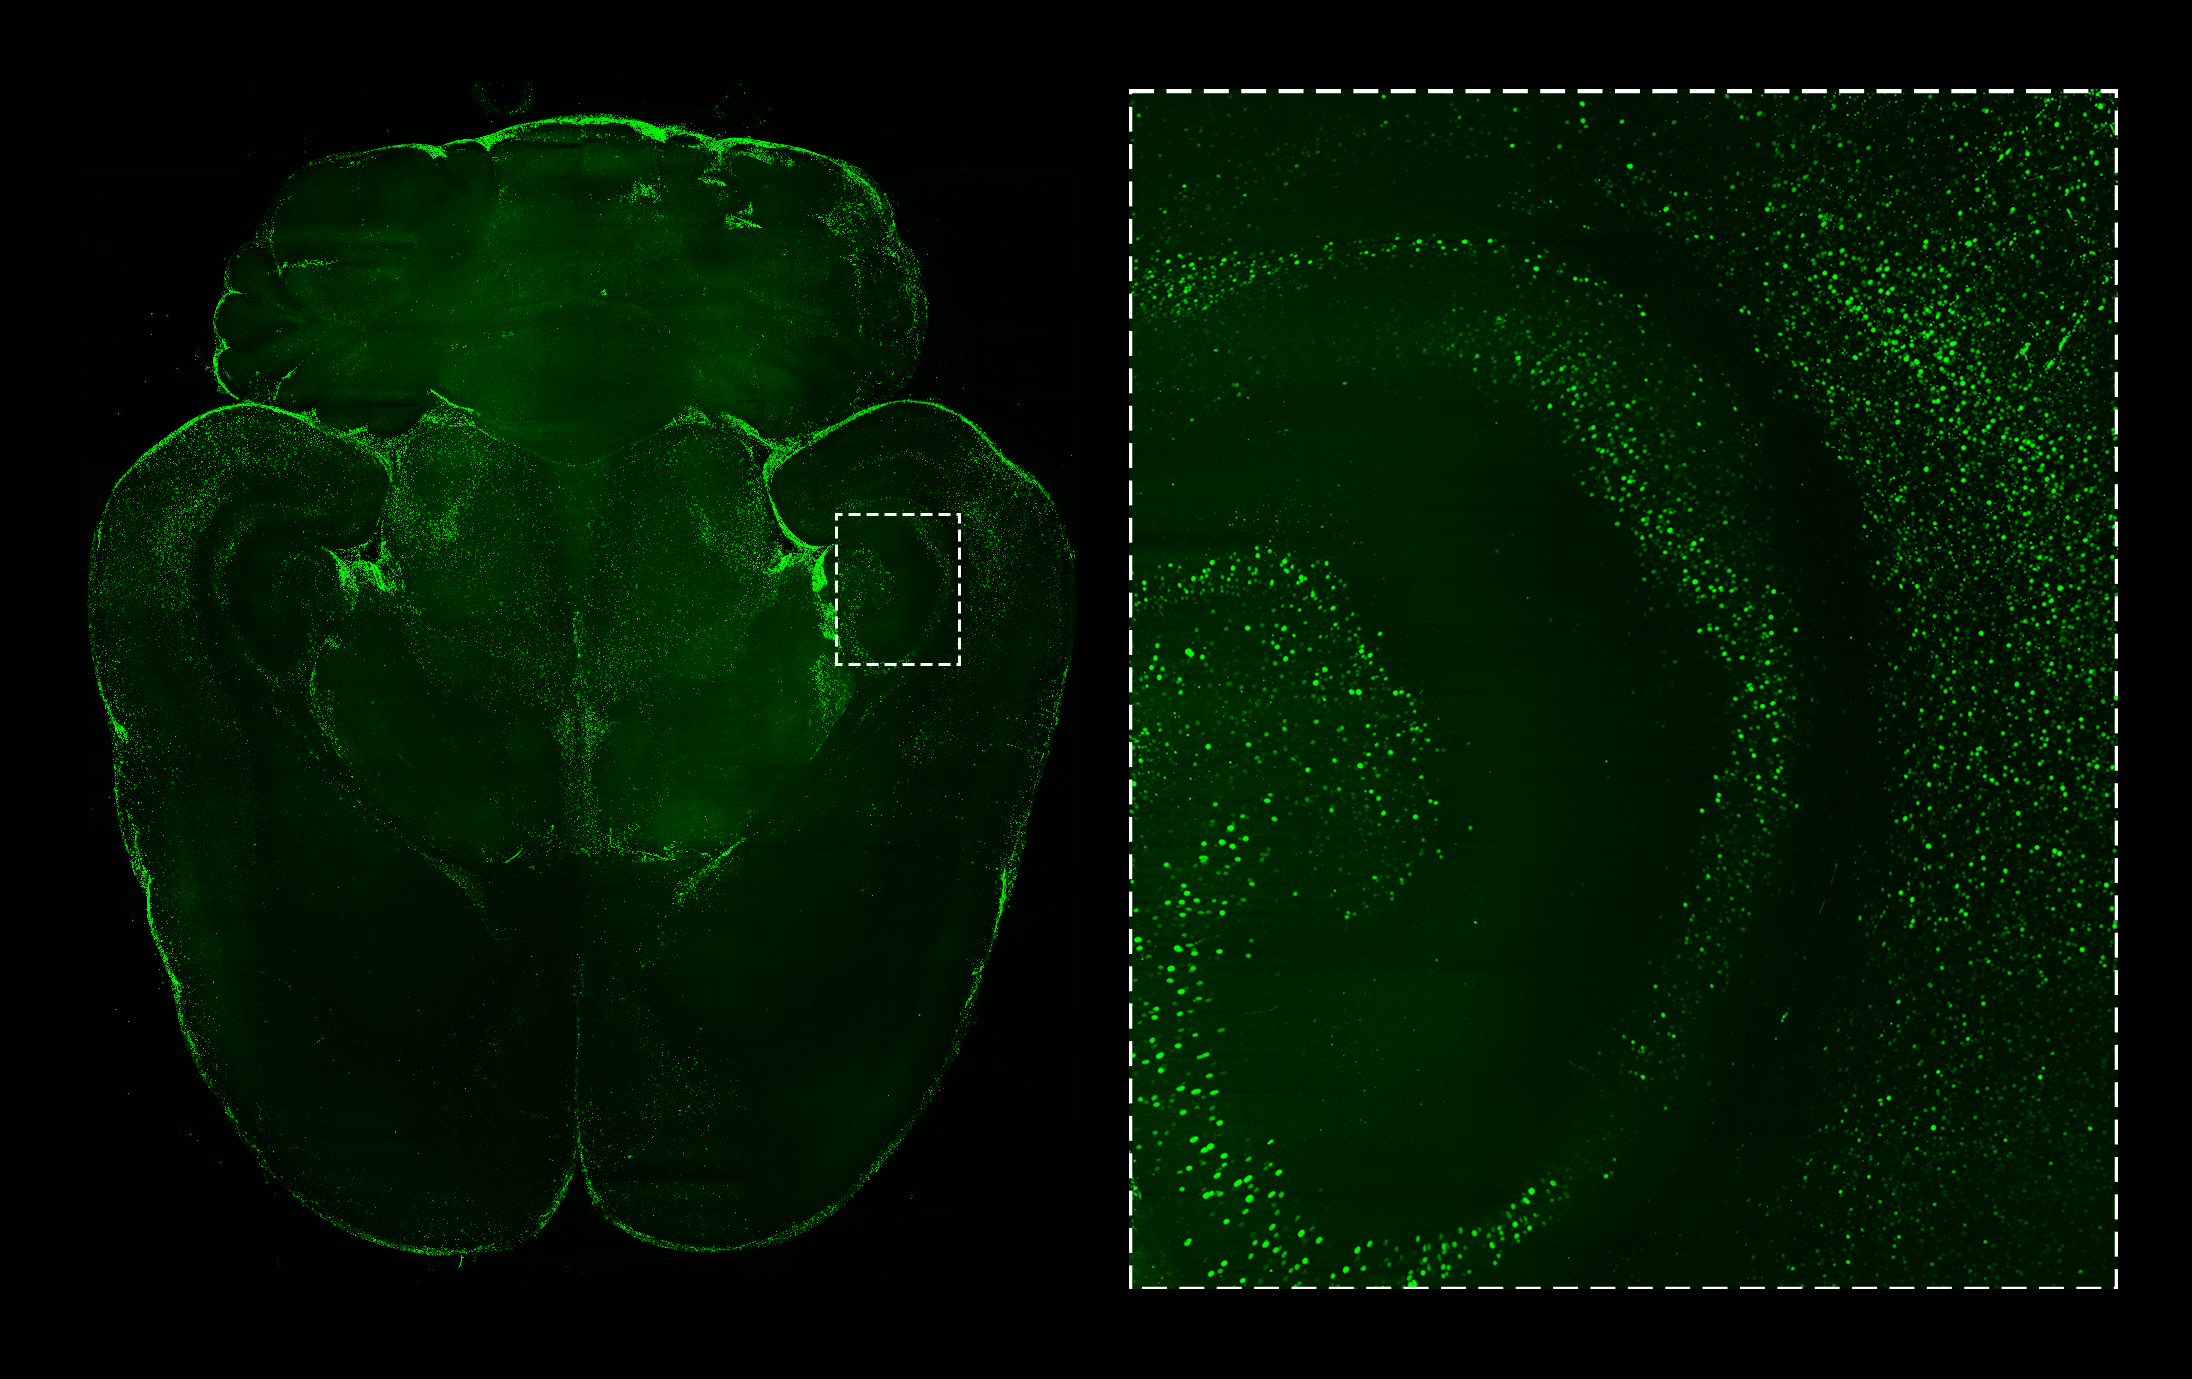

Overview of a rat brain section. The magnification shows the amygdala Rat Brain Markers This introductory level protocol describes the reagents, equipment, and techniques required to complete immunohistochemical staining of rodent brain tissue, using. In the central nervous system, granular cell tumors (a meningioma variant), followed by glial tumors, are the most common neoplasms in rats, whereas glial cell tumors are. This review focuses on advances in understanding the biology of innate immune cells. Rat Brain Markers.